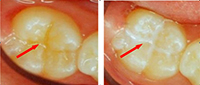

Οι προληπτικές καλύψεις οπών και σχισμών είναι υγρές ρητίνες οι οποίες τοποθετούνται στις μασητικές επιφάνειες των οπισθίων δοντιών. Σκοπός τους είναι να προστατέψουν το δόντι από την εμφάνιση τερηδόνας, εξαιτίας της κάλυψης που παρέχουν στις στενές οπές και σχισμές των δοντιών. Αυτό έχει ως αποτέλεσμα τον καλύτερο καθαρισμό με την οδοντόβουρτσα και την αποφυγή συσσώρευσης τροφών και μικροβίων στις περιοχές αυτές. Η προστασία που παρέχουν οι καλύψεις εφόσον παραμείνουν στη θέση τους είναι 100%.

Πότε και πώς γίνεται η τοποθέτησή τους;

Η τοποθέτησή τους γίνεται όταν έχει ολοκληρωθεί η ανατολή του δοντιού στο στόμα του παιδιού, οπότε η ηλικία που γίνεται η εφαρμογή τους διαφέρει από παιδί σε παιδί ανάλογα με το ρυθμό ανατολής των δοντιών του. Η τοποθέτησή τους είναι απλή και γρήγορη χωρίς να χρειάζεται αναισθησία ή τροχισμός του δοντιού. Εξίσου σημαντική είναι και η παρακολούθηση από τον παιδοδοντίατρο, διότι μερικές φορές οι προληπτικές καλύψεις μπορεί να αποκολληθούν από το δόντι, οπότε χρειάζεται η επανατοποθέτησή τους.

Οι προληπτικές καλύψεις οπών και σχισμών θα πρέπει να είναι μέρος ενός ολοκληρωμένου προληπτικού προγράμματος και να συνδυάζονται με τακτικές εφαρμογές φθορίου, ώστε να επιτυγχάνεται ακόμη μεγαλύτερη προστασία από την τερηδόνα.